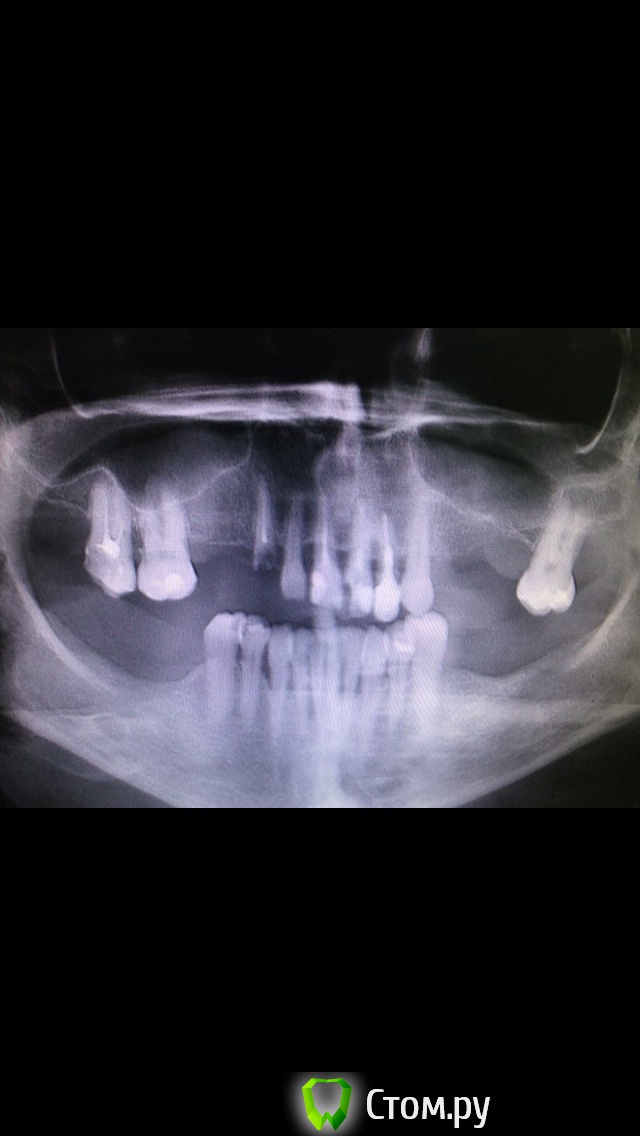

Mbegiev Опубликовано 28 ноября, 2014 Поделиться Опубликовано 28 ноября, 2014 (изменено) 2 синуслифтинга, 2 костных блока, времянки с опорой на свои зубы.Жду комментариев.P.S.: почему-то фото "после" перевёрнуто Изменено 28 ноября, 2014 пользователем Mbegiev 4 1 Ссылка на комментарий

SDC Опубликовано 29 ноября, 2014 Поделиться Опубликовано 29 ноября, 2014 Как Вы уговариваете пациентов расстаться с зубами? В данном случае были зубы с хорошим прогнозом, кмк. Ссылка на комментарий

SDC Опубликовано 29 ноября, 2014 Поделиться Опубликовано 29 ноября, 2014 (изменено) Не соглашусь с вами. Единственный зуб, который мог бы оставить, это 23, но смысла в одном этом зубе я не вижу. Уговаривать никого не приходится, предоставили пациенту комплексный план лечения, который его устроил.Смысл в том, что собственный зуб, с сохранными твердыми тканями и работающим пародонтом всегда лучше имплантата, в ближайшем будущем, я думаю, предстоит грандиозная переделка...Такое заключение я сделал на основании контрольного ОПТГ, где риплейсы уже потеряли кость в пришеечной области и имеются корни с вкладками без феррула. Изменено 29 ноября, 2014 пользователем SDC Ссылка на комментарий

Mbegiev Опубликовано 30 ноября, 2014 Автор Поделиться Опубликовано 30 ноября, 2014 (изменено) Смысл в том, что собственный зуб, с сохранными твердыми тканями и работающим пародонтом всегда лучше имплантата, в ближайшем будущем, я думаю, предстоит грандиозная переделка...Такое заключение я сделал на основании контрольного ОПТГ, где риплейсы уже потеряли кость в пришеечной области и имеются корни с вкладками без феррула.Да, я согласен с тем, что здоровый зуб с работающим пародонтом лучше любого импланта. В данной ситуации имела место подвижность I-II степени зубов верхней челюсти. По поводу убыли костной ткани. В этом случае была произведена одномоментная имплантация, и я вижу на снимке не убыль костной ткани, а несформированные лунки, так как орто сделано через месяц после установки.Спасибо за критику. Изменено 30 ноября, 2014 пользователем Mbegiev Ссылка на комментарий